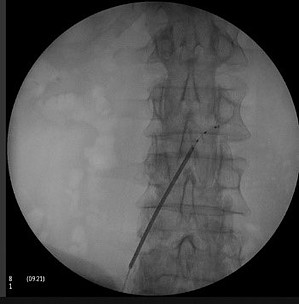

Rückenmarksstimulation

Vor allem bei bestimmten Schmerzsyndromen, die nicht oder nicht mehr ausreichend auf eine medikamentöse Therapie ansprechen, ist es möglich, durch die Rückenmarksstimulation eine Schmerzlinderung zu erzielen. Hierbei werden feine Elektroden in den Rückenmarkskanal eingesetzt, die elektrische Impulse abgeben. Das Einbringen der Elektroden kann in örtlicher Betäubung erfolgen. Die Elektroden werden durch einen Impulsgeber angesteuert, der unter die Haut am Gesäß oder an der Bauchwand der Patient:innen implantiert wird. Die abgegebenen elektrischen Impulse hemmen die Schmerzweiterleitung. Die Schmerztherapie durch Rückenmarksstimulation findet Anwendung nach Verletzung von Nerven oder des Rückenmarkes, aber auch bei Phantomschmerzen und bei behandlungsresistenten Schmerzen durch Durchblutungsstörungen bei Herzkrankheit (Angina Pectoris) und Gefäßkrankheit der Beine (pAVK). Bei der Gefäßkrankheit der Beine (pAVK) kann die Stimulation zudem dazu beitragen, die Durchblutung wieder zu verbessern und die Gliedmaßen zu erhalten. Die Nervenstrukturen bleiben bei der Rückenmarksstimulation erhalten, sodass die Stimulation jederzeit rückgängig gemacht werden kann. Die Einstellungen des Impulsgebers lassen sich von außen – auch durch die Patient:innen – verändern, sodass die Stimulation jederzeit an die Bedürfnisse der Patient:innen angepasst werden kann.